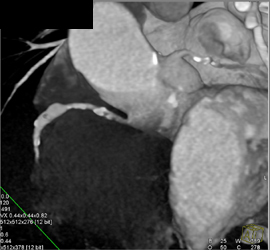

Diagnosis

Plaque in LAD